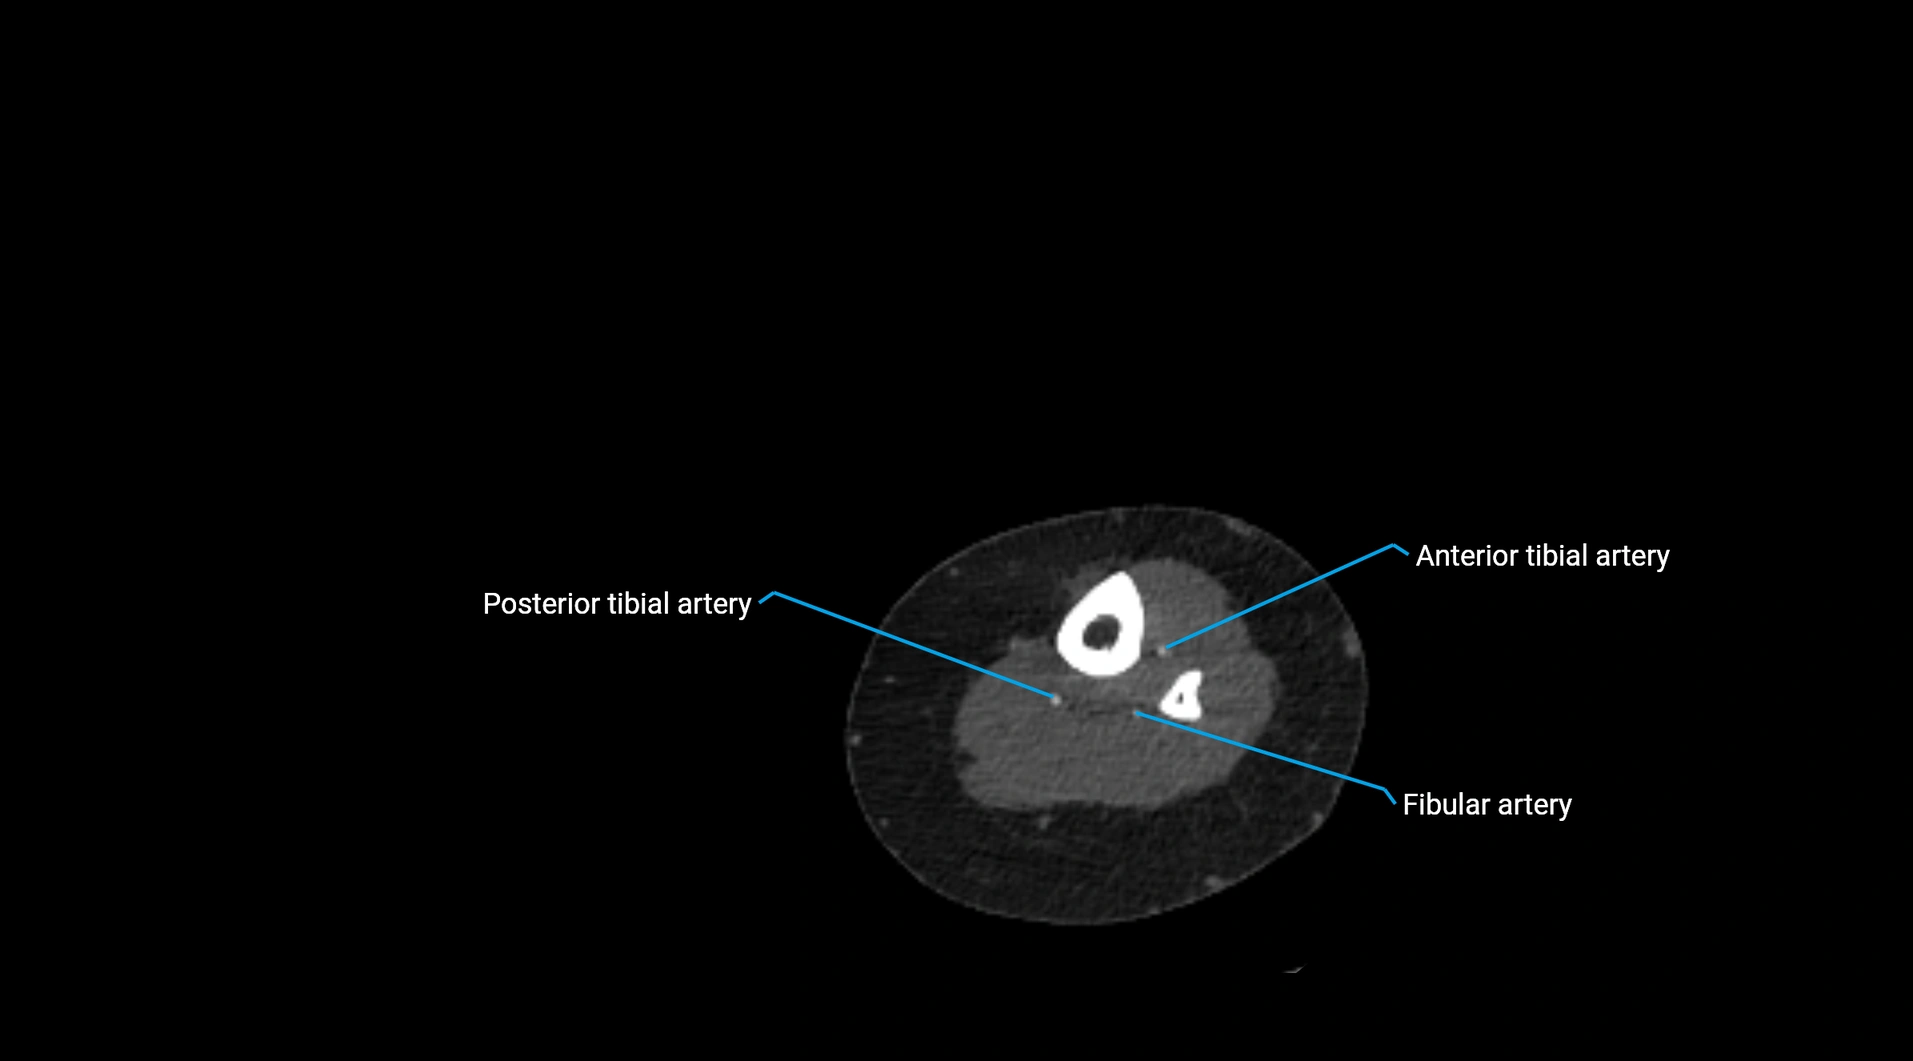

Contrast-enhanced CT (CTA):

• Gold standard for abdominal aortic imaging

• Provides excellent detail of lumen, wall, aneurysm, thrombus, and branch vessels

• Multiplanar and 3D reconstructions help in aneurysm measurement, stent graft planning, and dissection evaluation